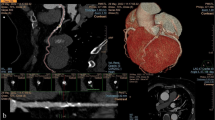

Non-calcified plaques were assessed quantitatively on an offline workstation (InSight, Neo Imagery, San Francisco, Calif.). The volumes of non-calcified plaques in the coronary artery wall were classified using thresholds of 0–130 HU. The outer border of the plaques was segmented manually, whereas the internal border between plaque area and contrast-enhanced vessel lumen was detected by the software and the plaque volume was calculated automatically (Fig. 1). The number, segmental location, and volumes of all non-calcified plaques, and the total non-calcified plaque volume burden per patient, were recorded.

Quantitative volumetry of non-calcified plaques. The quantitative volumetry was performed on an offline workstation (InSight, Neo Imagery, San Francisco, Calif.) The axial image at the height of the origin of the left coronary artery (left window) shows a large non-calcified plaque in the distal part of the left main coronary artery (arrow). Volumetry was conducted semi-quantitatively, segmenting the soft plaque borders by hand, whereas the software measured plaque volume automatically according to predefined thresholds (right window, see ellipsis for results)

According to the CT findings, the detected plaques were divided into three groups: purely calcified plaques (CP); mixed plaques (MP); and purely non-calcified plaques (NCP). Mixed plaques were defined as plaques with calcifications and non-calcified components in direct vicinity to each other. The quantification of non-calcified plaques was done only for the subgroup of patients, who presented real non-calcified plaques. In patients with mixed plaques, i.e., plaques consisting of calcified and non-calcified components, the volume of non-calcified plaque burden could not be assessed by the analysis software. The "total plaque volume", given in cubic millimeters, was defined as the sum of calcium volume equivalent and the volume of the non-calcified plaques.